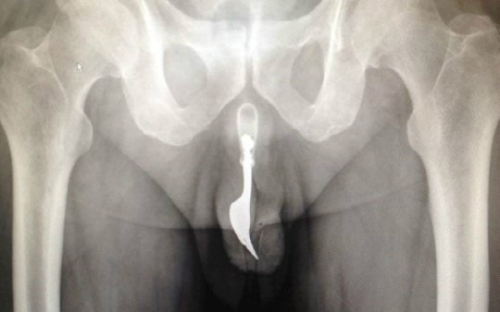

자신의 성기 안에 포크를 넣은 남성이 병원에서 수슬을 받았다.

19일(현지시간) 영국매체 데일리메일에 따르면 호주 캔버라에 사는 70대 남성이 성적쾌감을 위해 10cm 길이의 포크를 요도안으로 집어 넣었다가 12시간동안 극심한 고통에 시달린 나머지 병원신세를 졌다.

의료진은 다량의 윤활제를 투입하고 핀셋으로 포크를 '무사히' 빼내는 데 성공했으며 이 남성은 입원 치료없이 귀가했다.

사진=국제외과학술지